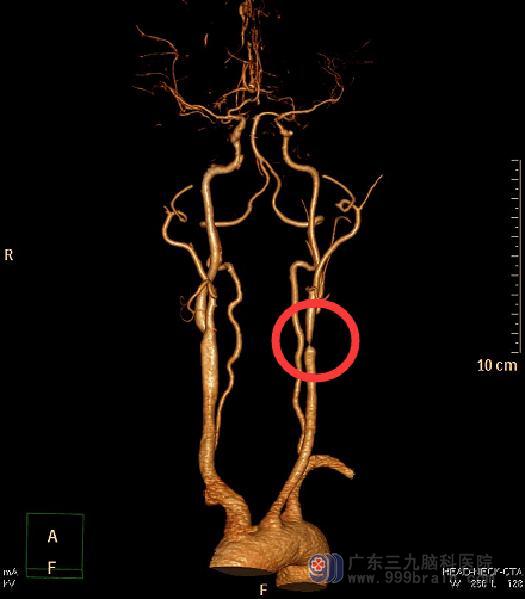

广东三九脑科医院头颅CTA检查提示:左侧颈内动脉颈段起始部局部狭窄闭塞;左侧颈外动脉起始部明显狭窄,狭窄面积约65.5%。全脑血管造影显示:1、左侧颈内动脉起始部闭塞,主要由左侧颈外动脉脑膜中动脉、左侧椎动脉肌支-枕动脉-颈内动脉代偿供血;2、左侧椎动脉起始重度狭窄,狭窄程度约62%,狭窄长度约3mm;3、左侧颈外动脉重度狭窄,狭窄程度约70%,狭窄长度约5mm;4、右侧颈内动脉起始部小斑块形成。

由综合神经外科鲁明主任主刀,在全麻下行左侧颈内动脉粥样斑块取出+内膜剥脱术,术中见颈内动脉起始段黄白色粥样斑块,质硬,边界清,长度约5cm,予取出斑块,剥除内膜,连续缝合颈内动脉切口,手术过程很顺利。术后陈老师语言功能明显改善。复查头颅CTA提示:左侧颈内动脉颈段起始部原狭窄闭塞段现管腔通畅,较邻近管腔较宽。